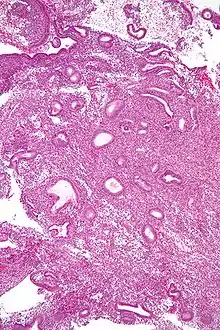

![]() صورة مجهرية توضح خزعة بطانة الرحم لعينة تُشير إلى فرط تنسج بطانة الرحم حيث نسبة الغدة إلى السدي كما هي لكن الغدد لها شكل غير منتظم و/أو مُتسعة. صبغة H&E | |